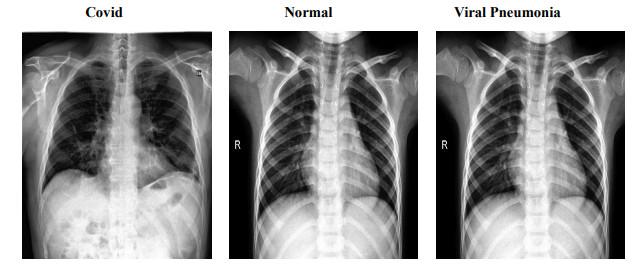

The COVID dataset is a crucial resource comprising 317 JPEG images, meticulously categorized into 'COVID', 'Normal', and 'Viral Pneumonia'. Organized into 'train' and 'test' branches, this dataset ensures streamlined access and efficient navigation, facilitating both model training and validation. Originating from Kaggle, this collection provides a foundational platform for developing sophisticated models aimed at distinguishing these respiratory conditions effectively. Figure 1 presents sample images from each category, illustrating the distinct visual features that help models differentiate between COVID-19, normal lung conditions, and viral pneumonia. These sample images reflect the dataset’s capacity to represent unique patterns across categories, aiding in model training. The 'train' branch includes 111 images classified as 'COVID', 70 as 'Normal', and 70 as 'Viral Pneumonia', providing a rich variety of data to enhance model learning capabilities through exposure to diverse patterns and features inherent in different conditions. Conversely, the 'test' branch is critical for evaluating model robustness and accuracy on previously unseen data, comprising 26 'COVID' images, 20 'Normal', and 20 'Viral Pneumonia'. This setup ensures that the models can be rigorously tested to assess their performance accurately.

Figure 1: Sample Images from COVID Dataset